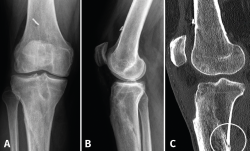

A los 6 meses de la cirugía consulta por dolor de inicio brusco, a la carga, sin antecedente traumático. A la exploración presenta subderrame con dolor difuso que dificulta la exploración. La radiografía (Rx) y la resonancia magnética (RM) (Figura 1) muestran una fractura metafisodiafisaria espiroidea proximal de tibia, no desplazada. Ante estos hallazgos, se inicia magnetoterapia, carga parcial según la tolerancia, inmovilización con ortesis articulada y se suspende el trabajo de tonificación en cadena abierta. En el control realizado a las 2 semanas refiere persistencia del dolor a la carga; se realiza una tomografía axial computarizada (TAC) que informa de una fractura metafisodiafisaria de tibia proximal no desplazada, con un trazo más evidente en la zona posterolateral, en proceso consolidativo intermedio, con inicio del trazo en el túnel tibial. Una segunda TAC, realizada a los 2 meses, muestra la consolidación de la fractura de tibia. Clínicamente, presenta gonalgia difusa y atrofia muscular; tolera la carga con una muleta. Se retira el inmovilizador continuando con la rehabilitación. Actualmente, el paciente está de alta laboral con secuelas (baremo), alta que impugnó y perdió.

Figura 1. A y B: la radiografía muestra una fractura metafisodiafisaria espiroidea proximal tibia, no desplazada; C: en la resonancia magnética se ve la línea de fractura que afecta la cortical posterior de la tibia.